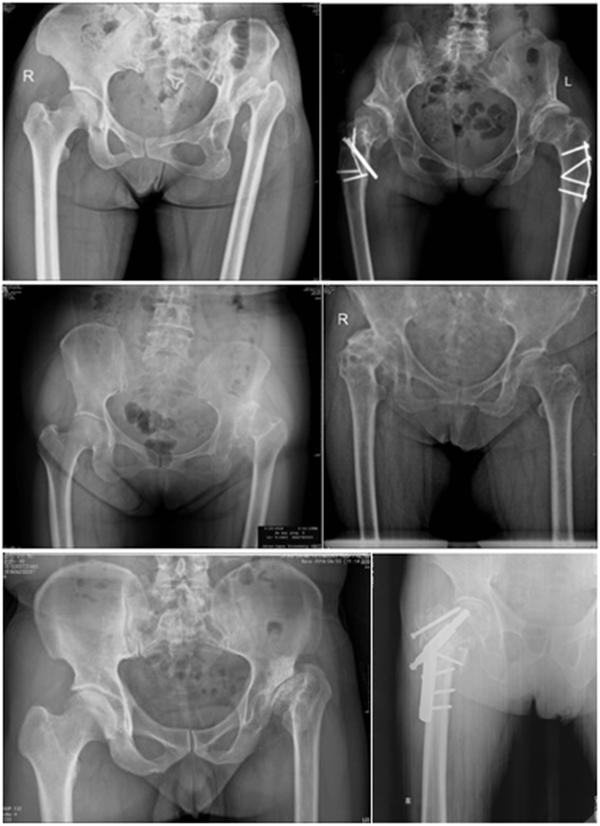

Ⅳ、股骨干畸形

(1)前倾异常增大

先股骨侧操作,根据联合前倾角及各向稳定性决定髋臼前倾,以达最佳稳定。

(2)髓腔狭小

细长股骨柄与狭窄髓腔匹配。

(3)股骨成角畸形

程度轻,且远离假体安放位置:近端固定短柄假体或小号骨水泥型假体。

严重且靠近假体安放位置:必须行截骨矫正,以获得良好的对线。

③近端的重建:纠正性截骨,短缩截骨。

纠正性截骨的要求是:

①在畸形最严重的部位纠正对线不良;

②最大限度保留骨质;

③截骨部位牢固固定;

④使用长柄假体跨越截骨端。

股骨截骨的不同方法:

股骨近端截骨重建——截骨方式:横形、斜形、阶梯式及双V形截骨

优点:不改变股骨近端的解剖,保持臀中肌附丽点完整,截骨后能矫正股骨的前倾角,是较为理想的股骨缩短方法。

缺点:①骨折——截骨两端捆钢丝;②截骨端不稳定,术后骨折不愈合——足够长的远端固定型非骨水泥型假体或组配型假体,假体长度足够,避免型号过小,必要时使用骨板加强固定;③失血多、时间长。